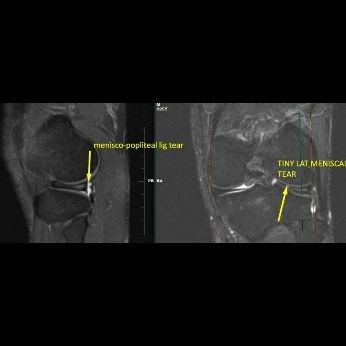

A tiny grade III tear of the inner zone of posterior horn of lateral meniscus associated with grade I horizontal signal changes within posterior horn and body

Longitudinal tear involving the lateral menisco popliteal ligament at superior and inferior fascicle.